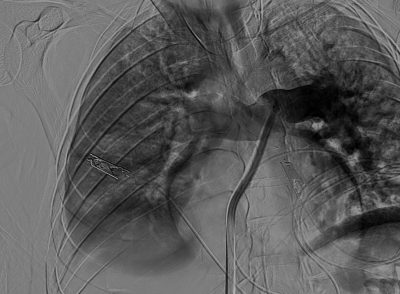

سجل مجمع الدمام الطبي أحد مكونات تجمع الشرقية الصحي ، إنجازاً طبياً نوعياً بعد نجاح فريق الأشعة التداخلية في إنقاذ حياة مريض كان يعاني من جلطة رئوية حادة وكبيرة شكّلت خطراً مباشراً على حياته ، وذلك باستخدام تقنية طبية متقدمة دون الحاجة إلى جراحة قلب مفتوح .

وكان المريض قد نُقل بشكل إسعافي من أحد المستشفيات وهو في حالة حرجة ، نتيجة معاناته من ضيق شديد في التنفس وانخفاض حاد في مستوى الأكسجين ، إثر انسداد كامل في الشريان الرئوي الرئيسي بسبب خثرات وريدية عميقة ظهرت بعد خضوعه لعملية منظار لمفصل الركبة.

وبفضل سرعة الاستجابة وجاهزية فريق الأشعة التداخلية جرى التدخل العلاجي العاجل وفتح الشريان الرئوي وسحب الجلطة بالكامل بدقة عالية ، ما أدى إلى تحسّن فوري في العلامات الحيوية واستقرار الحالة دون تسجيل أي مضاعفات